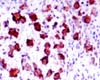

Bacteria that cause the bubonic plague may be more virulent than their close relatives because of a single genetic mutation, according to research published in the May issue of the journal Microbiology.

"The plague bacterium Yersinia pestis needs calcium in order to grow at body temperature. When there is no calcium available, it produces a large amount of an amino acid called aspartic acid," said Professor Brubaker from the University of Chicago, USA. "We found that this is because Y. pestis is missing an important enzyme."

Bubonic plague has killed over 200 million people during the course of history and is thus the most devastating acute infectious disease known to man. Despite this, we are still uncertain about the molecular basis of its extraordinary virulence.

"Y. pestis evolved from its ancestor Y. pseudotuberculosis within the last 20,000 years, suggesting its high lethality reflects only a few genetic changes. We discovered that a single mutation in the genome of Y. pestis means the enzyme aspartase is not produced," said Professor Brubaker.

Aspartase is present in almost all bacteria but it is curiously absent in many pathogenic types. These include mycobacteria that are pathogenic to man, Francisella tularensis and rickettsiae (both of which cause diseases transmitted to humans via insects). "This suggests that the absence of aspartase may contribute to serious disease," said Professor Brubaker.

Aspartase digests aspartic acid. Because Y. pestis doesn't have the enzyme, it produces much more aspartic acid than is required by the person infected. This may cause an imbalance to the host amino acid pools. "If this is the case then we might be able to reduce the death rates of these diseases by developing a treatment that removes some of the extra aspartic acid," said Professor Brubaker.